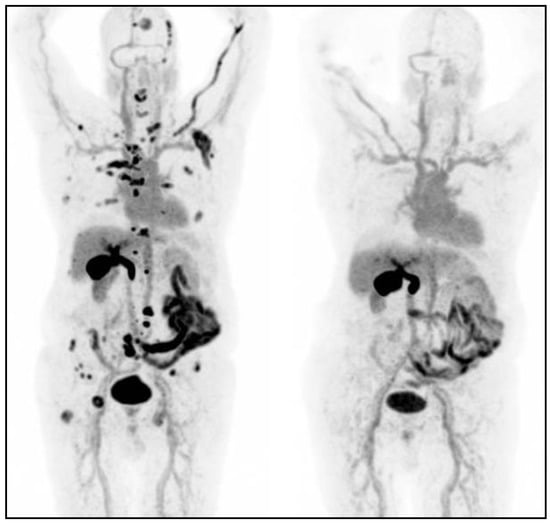

- Nilica, B.; Waitz, D.; Stevanovic, V.; Uprimny, C.; Kendler, D.; Buxbaum, S.; Warwitz, B.; Gerardo, L.; Henninger, B.; Virgolini, I.; et al. Direct comparison of 68Ga-DOTA-TOC and 18F-FDG PET/CT in the follow-up of patients with neuroendocrine tumour treated with the first full peptide receptor radionuclide therapy cycle. Eur. J. Nucl. Med. Mol. Imaging 2016, 43, 1585–1592. [Google Scholar] [CrossRef]

- Muffatti, F.; Partelli, S.; Cirocchi, R.; Andreasi, V.; Mapelli, P.; Picchio, M.; Gianolli, L.; Falconi, M. Combined 68Ga-DOTA-peptides and 18F-FDG PET in the diagnostic work-up of neuroendocrine neoplasms (NEN). Clin. Transl. Imaging 2019, 7, 181–188. [Google Scholar] [CrossRef]